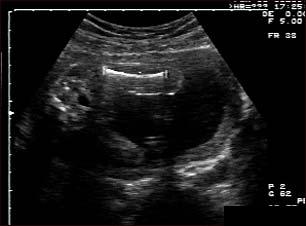

Ecografia fetala